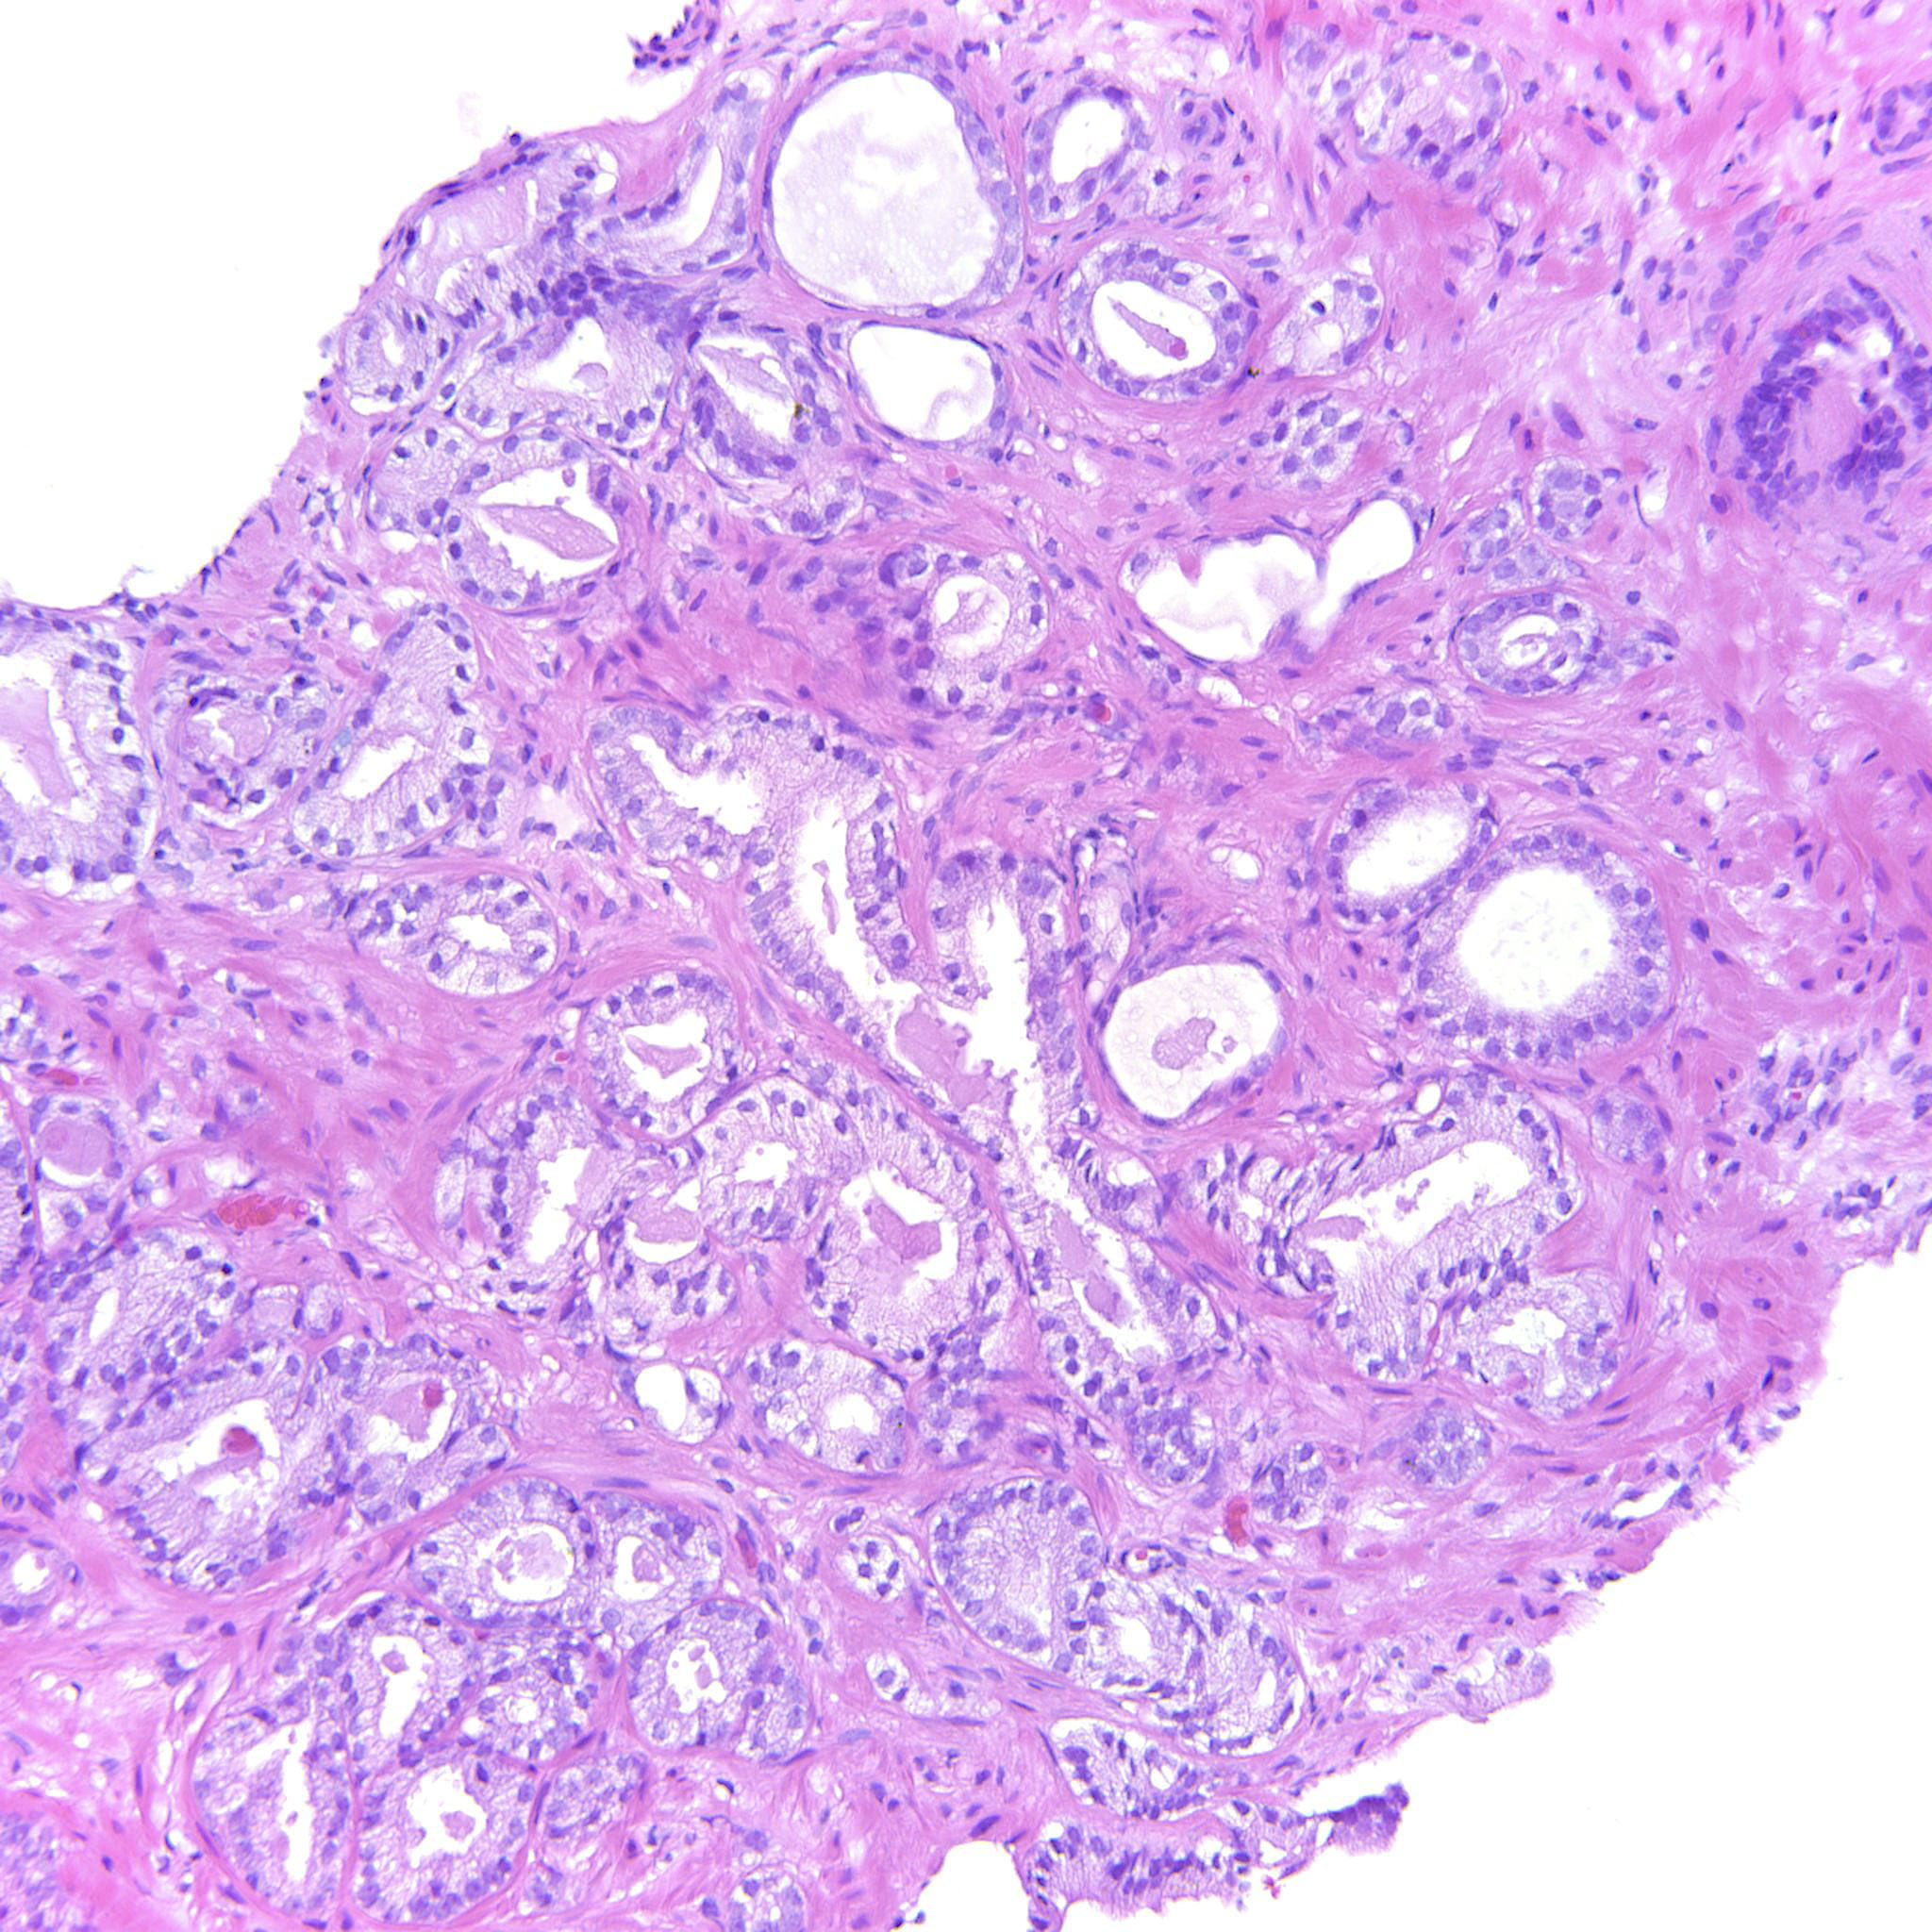

Prostate cancer grading

Case ID: 343